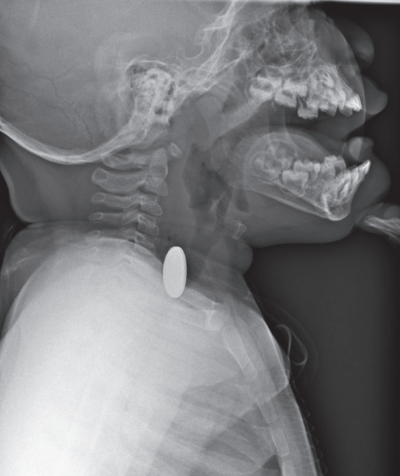

11 か月の男児。パッケージから出したばかりのコイン型リチウム電池を飲み込んだため両親に連れられて来院した。

体温 36.2 ℃。 心拍数 120/分、 整。 血圧80/56 mmHg。呼吸数 32/分。SpO₂ 98 %(room air)。機嫌はよく、顔色は良好である。努力呼吸を認めず、呼吸音に異常を認めない。来院時の胸部エックス線写真の背臥位正面像と背臥位側面像を別に示す。

この患児に適切な対応はどれか。